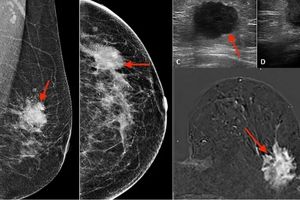

مرکز دکتر راضیه حیدری متخصص رادیولوژی با رویکردی علمی، تخصصی و بیمارمحور به عنوان یکی از معتبرترین مراکز تشخیص و غربالگری بیماریهای پستان در شرق تهران شناخته میشود. ترکیبی از دانش روز، تجهیزات پیشرفته و تیمی از متخصصان با تجربه این مرکز را به انتخاب اول بسیاری از بانوان در منطقه تبدیل کرده است.

استفاده از تجهیزات پیشرفته تصویربرداری

در این مرکز از تکنولوژیهای نوین همچون ماموگرافی دیجیتال فولفیلد (FFDM) و سونوگرافی پستان با پروب تخصصی بهره گرفته میشود که امکان تشخیص زودهنگام و دقیق را فراهم میسازند. این موضوع بهویژه برای تشخیص تودههای کوچک و پنهان بسیار حیاتی است.